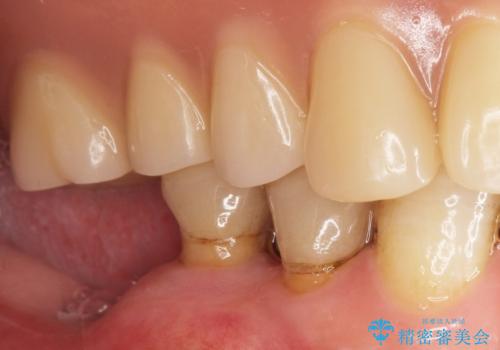

奥歯のインプラント 70代男性

- 奥歯の違和感を主訴に来院された患者様です。

精査したところ、右下の奥歯は大きなう蝕により保存不可能な状態でした。

患者様のご希望により、抜歯後インプラント治療を行いました。